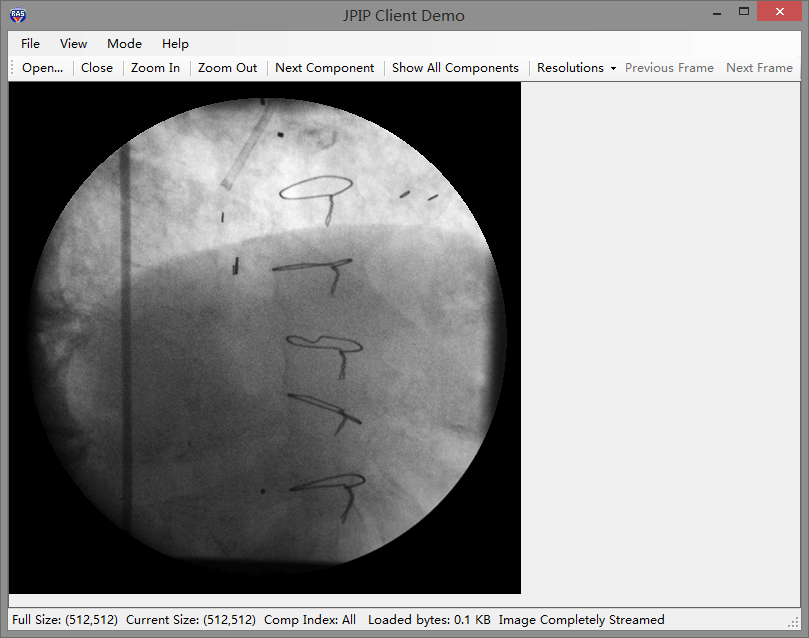

| hl7(heath_level_seven卫生信息传输标准)完全支持 | 高质量html5支持 | jpip支持,帮助您创建切片工作站 |

leadtools 完整的jpip协议,帮助您创建jpip 服务器和客户端,使您能够快速的开发出一个完整的切片工作站,各种细胞切片、组织切片都可以无延迟浏览。